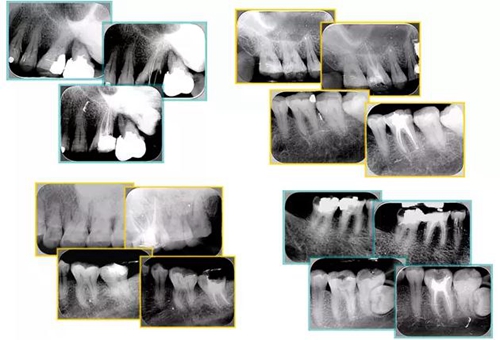

28.jpg

(二)找到全部根管口

29.jpg

( 4 )結(jié)論: ① 中心法則:髓室底通常位于釉牙骨質(zhì)界水平的牙齒的中心。 ② 同心法則:髓壁經(jīng)常在 CEJ 的水平與牙齒外形呈同心性。 ③ CEJ 法則: CEJ 是最確切的可重復(fù)利用的髓腔定位標(biāo)志。

2 、 根管口與髓室底的關(guān)系

30.jpg

3 、全部根管的發(fā)現(xiàn)

31.jpg

(三)對(duì)稱性的現(xiàn)象

切割樣本顯示對(duì)稱性,下后磨牙近遠(yuǎn)中中線兩側(cè)根管口對(duì)稱現(xiàn)象。

對(duì)稱性現(xiàn)象 1 :除上頜后磨牙外,根管口距離近遠(yuǎn)中向穿過髓室底的連線的距離相等。

對(duì)稱性現(xiàn)象 2 :除上頜后磨牙外,根管口位于近遠(yuǎn)中向穿過髓室底中心連線的垂直線上。